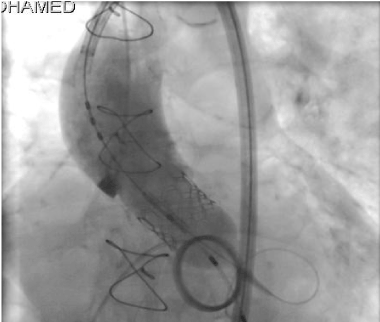

Under temporary pacing, we did first aortic balloon valvuloplasty using Edward 20 mm balloon, then, we decided to proceed with size #23 Edward Sapein bioprothetic and paln to overinflated with extra 2 cc of contrast. Edward size # 23 mm successfully deployed under fluoroscopy and transthoracic echocardiography with good result (Figure 2). The immediate post TAVI hemodynamic and echocardiography Doppler showed complete remission of the transaortic valve pressure gradient, no aortic regurgitation and no paravalvular leak.

Figure 2. TAVI Deployement.